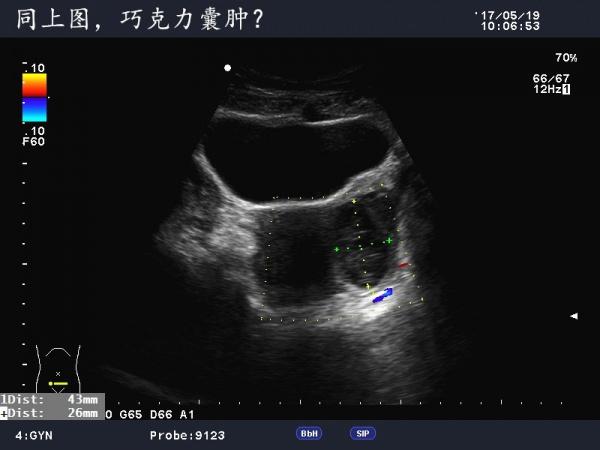

这是巧克力囊肿吗?

患者女,40Y,因下腹部疼痛就诊,最近一次月经来潮量少且疼痛厉害,以往基本上正常。

于月经第11天行B超检查。

不是很典型的巧克力囊肿,可以随访复查看看

可定期复查,黄体不除外